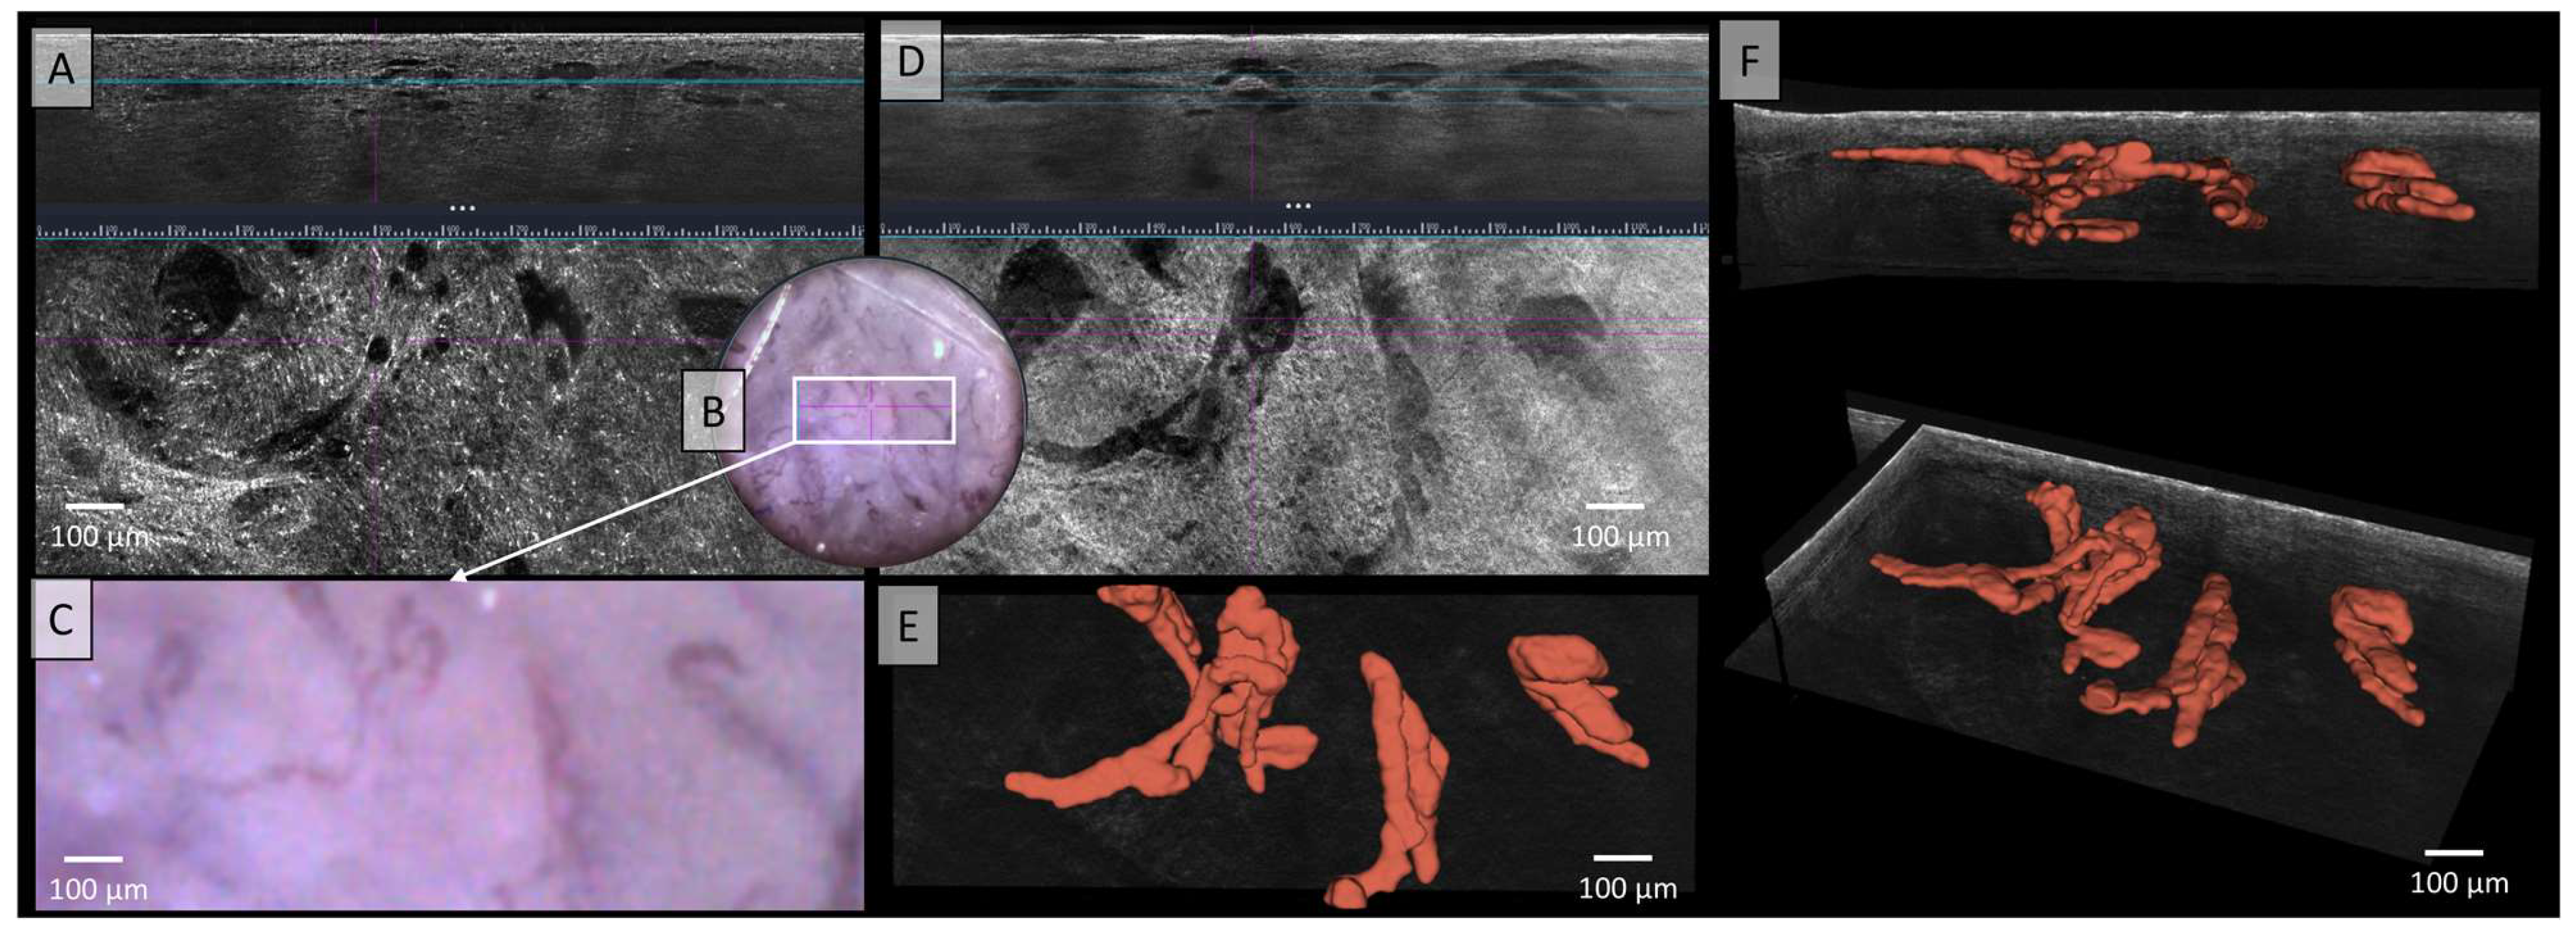

In Figure 2, no correlation between the LC-OCT and dermoscopic images can be established, likely due to pigment melanin obscuring vascular architecture. In the two illustrated LC-OCT image planes, a mixture of vessel structures can be observed, with some appearing elongated at deeper levels, while others form clusters of convoluted vascular conglomerates. No clear correlations can be drawn from the two available images. Additionally, the vessels do not display a uniform or consistent morphology, but rather exhibit marked polymorphism. The description of Figure 2 already highlighted the polymorphic nature of the vessels, characterized by elongated structures and densely arranged vascular conglomerates in deeper tissue layers. However, the relationship between these vessels remained unclear. The spatial arrangement and connections between the vessels are now clearly visualized (Figure 2E,F). A pronounced polymorphism of the vessels is observed across multiple levels and layers, with a diffuse arrangement and a wide range of vessel calibers, varying from very large to very small. However, the blood flow of this melanoma showed a medium to low velocity of the blood cells in the video (see Video S1).

Figure 2.

Vessels of a malignant melanoma in Line-field confocal optical coherence tomography (LC-OCT); (A) Normal rendering (deepGaussian) shows a diffuse arrangement of polymorphic vascular structures consisting of linear vessel parts as well as clumsy conglomerates in both vertical (top image, LC-OCT image size: 1.2 mm (width) × 0.4 mm (height)) and horizontal section (middle image, LC-OCT image size: 1.2 mm (width) × 0.5 mm (height)), the connections cannot be clearly identified, zoom on integrated LC-OCT dermoscopy ((B,C) bottom image, image size: 1.2 mm (width) × 0.5 mm (height)) shows no vessels; the white rectangle represents the area of taken LC-OCT scan. (D) Minimum rendering with large vessel thickness (top and middle image). Three-dimensional (3D) visualisation shows: (E) Horizontal view (bottom image, LC-OCT image size: 1.2 mm (width) × 0.5 mm (height)) on the 3D segmented vessels; (F) two different perspectives of the 3D reconstruction show that the vessels are primarily arranged in one plane (LC-OCT images size: 1.2 (width) × 0.5 (length) × 0.5 (height) mm3).

Figure 2A–D illustrates a diffuse arrangement of polymorphic vascular structures, comprising both linear vessel segments and irregular conglomerates, with connections that are difficult to clearly discern. In contrast, the 3D visualization in Figure 2E,F allowed for a detailed representation of vessel organization and polymorphism, showing both linear and glomerular vessels. A review of the literature on melanoma-associated vessels reveals that the term “polymorphic vessels” is frequently encountered, with the most common combination being dotted vessels and linear–irregular vessels [45]. Furthermore, Welzel et al. were able to demonstrate the polymorphism of blood vessels using D-OCT in comparison to healthy skin. In this study, a higher prevalence of linear and coiled vessels, some of which resemble glomerular vascular tufts, was observed when compared to healthy skin [40]. Additionally, the presence of distinctly varying vessel calibers is well-documented in the literature and is characteristic of melanomas and their vascular polymorphism [43]. However, little has been published on the distribution of vessels across multiple layers, likely due to the limited number of 3D visualizations of skin in existing studies. Future developments in LC-OCT technology could include the integration of AI-analysis capable of automatically detecting vessels in LC-OCT images. Our findings could be used as a foundation for the future training of AI models, since manual segmentation is time consuming. This AI feature would then not only assist in assessing the vasculature of skin tumors for treatment planning and monitoring but could also play a valuable role in the diagnosis and follow-up of inflammatory diseases. Moreover, with trained AI models, the 3D reconstruction of multiple skin tumors is possible in a very short time. Then our preliminary findings on 3D skin tumor vascularization could be confirmed in a larger study cohort.